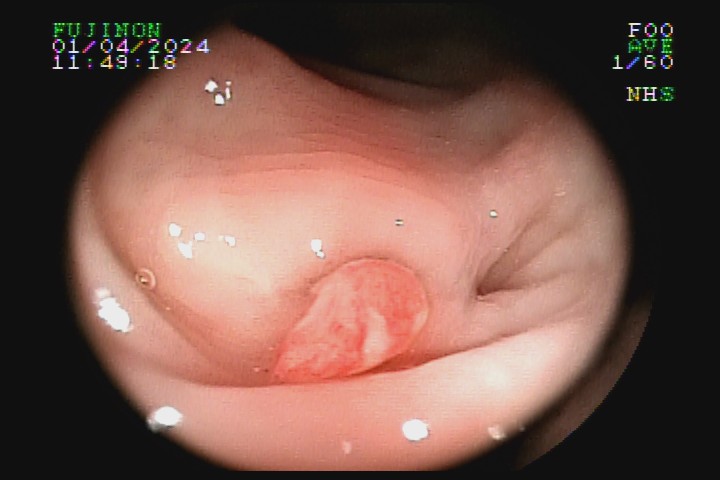

A diverticulose é uma doença adquirida, frequente entre pessoas mais idosas. Acredita-se que tenha como principal fator etiológico hábitos dietéticos relacionados com o refinamento da dieta industrializada. Pode ter uma evolução benigna por toda a vida e ser totalmente assintomática, mas pode também caracterizar-se como doença de sinais e sintomas agressivvos, com considerável morbidade e mortalidade devido às suas principais complicações: inflamação e sangramento.

A diverticulose cólica é consequência da herniação da mucosa do intestino grosso por entre as fibras musculares da parede intestinal. A diverticulose do cólon esquerdo complica mais com inflamação, e a diverticulose do cólon direito complica mais com sangramento.